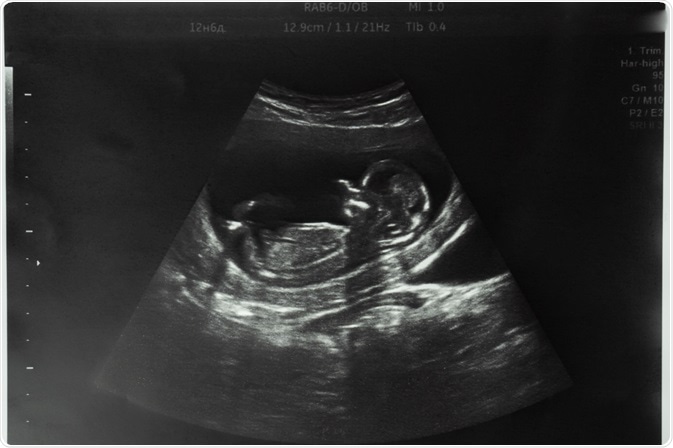

One of the most exciting things to look forward to when a new baby is about to be born is the question, will it be a girl or a boy? While many and astonishingly diverse answers have been offered to this query, the use of modern ultrasonography offers an accurate answer from early pregnancy onwards.

Ultrasound sex determination

High-resolution ultrasound now allows fetal morphology to be visualized clearly, thus paving the way for fetal sex determination at an earlier date during the first trimester. At an embryonic length (crown-rump length, CRL) of 76 mm or more, the chances of identifying the fetal sex accurately are 99% or more.